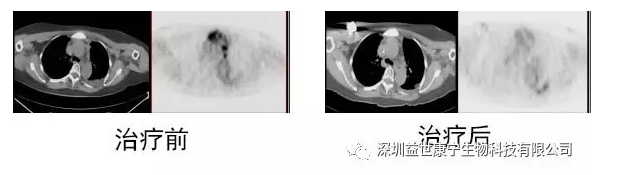

以下左图为治疗前情况,复发后转移病灶非常明显。右图为10个月ACTL科研治疗后复查结果,转移病灶明显消失。经5年余追踪观察,无复发迹象。